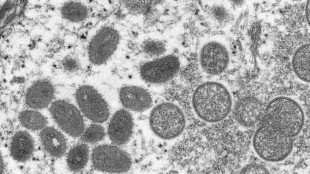

Variole du singe: une maladie le plus souvent bénigne

La variole du singe, dont plusieurs cas ont été détectés en Europe et en Amérique, est une maladie rare originaire d'Afrique dont on guérit en général spontanément. Pour l'heure, l'OMS dit ne pas redouter de pandémie.

Variole du singe: 16 cas confirmés en France

Variole du singe: premières vaccinations de personnes cas contact en France

Deux premières personnes, considérées comme ayant eu un contact à risque avec un malade de la variole du singe, ont été vaccinées vendredi à Paris, à l'hôpital Bichat, a-t-on appris auprès de la Direction générale de la Santé.

Variole du singe: plus de 200 cas confirmés dans le monde

Le nombre de cas confirmés de variole du singe dans le monde a atteint 219 mercredi hors des pays où la maladie est endémique, selon un bilan diffusé par l'agence de l'Union européenne chargée des maladies.

Variole du singe: Roche développe des tests PCR de détection du virus

Le géant pharmaceutique suisse Roche a annoncé mercredi avoir développé des tests PCR de détection du virus de la variole du singe, après l'apparition de plusieurs cas dans des régions du monde où la maladie n'est pas courante.

Variole du singe: 5 cas en France, assez de vaccins pour les cas contact, dit Bourguignon

La France compte actuellement cinq cas "avérés" de variole du singe, a indiqué mercredi la nouvelle ministre de la Santé Brigitte Bourguignon, précisant que le pays disposait des stocks nécessaires pour vacciner les cas contact comme le recommandent les autorités sanitaires.

Variole du singe: une maladie rare dont on guérit en général spontanément

La variole du singe, dont plusieurs cas ont été détectés en Europe et en Amérique du Nord, est une maladie rare originaire d'Afrique dont on guérit en général spontanément.

Variole du singe: la Haute autorité de santé recommande de vacciner les cas contacts

Face aux cas de variole du singe, désormais trois confirmés en France, la Haute autorité de Santé a recommandé mardi de vacciner les adultes, y compris des professionnels de santé, ayant eu un contact à risque avec un malade.

Les Etats-Unis veulent vacciner les cas contacts contre la variole du singe

Les Etats-Unis se préparent à vacciner les personnes ayant été en contact proche avec des patients atteints de la variole du singe, au moment où le pays, qui compte aujourd'hui cinq cas probables ou confirmés, s'attend à voir leur nombre augmenter.

Variole du singe: de nouveaux cas chaque jour au Royaume-Uni

Le Royaume-Uni enregistre chaque jour de nouveaux cas de variole du singe, a indiqué dimanche une responsable de l'Agence britannique de sécurité sanitaire, un sujet que le gouvernement dit prendre "très au sérieux".

La variole du singe s'étend en Europe

Après les Etats-Unis et plusieurs pays européens, notamment l'Espagne et le Portugal, la France et l'Allemagne sont touchées à leur tour par la variole du singe. Si la plupart des cas sont pour l'heure sans gravité, cette vague inhabituelle hors d'Afrique préoccupe les autorités sanitaires.

La variole du singe gagne l'Allemagne et la France

Après les Etats-Unis et plusieurs pays européens, la France et l'Allemagne sont touchées à leur tour par la variole du singe. Si la plupart des cas sont pour l'heure sans gravité, cette vague inhabituelle hors d'Afrique préoccupe les autorités sanitaires.

La France à son tour touchée par la variole du singe

Après les Etats-Unis et plusieurs pays européens, la France est touchée à son tour par la variole du singe: une situation "inédite" puisque les cas recensés sont sans lien direct avec des personnes de retour de zone endémique.

Variole du singe: un premier cas d'infection confirmé en France

Un premier cas confirmé de variole du singe a été détecté jeudi en Ile-de-France, ont annoncé vendredi les autorités sanitaires.